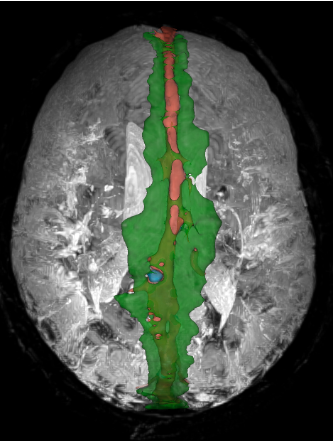

Segmentation tools for the quantification of peri-sinus space using non-invasive MRI developed by Dr. Kilian Hett.

Choroid plexus segmentation

A segmentation tool for the delineation and volumetric quantification of the choroid plexus developed by Dr. Kilian Hett.